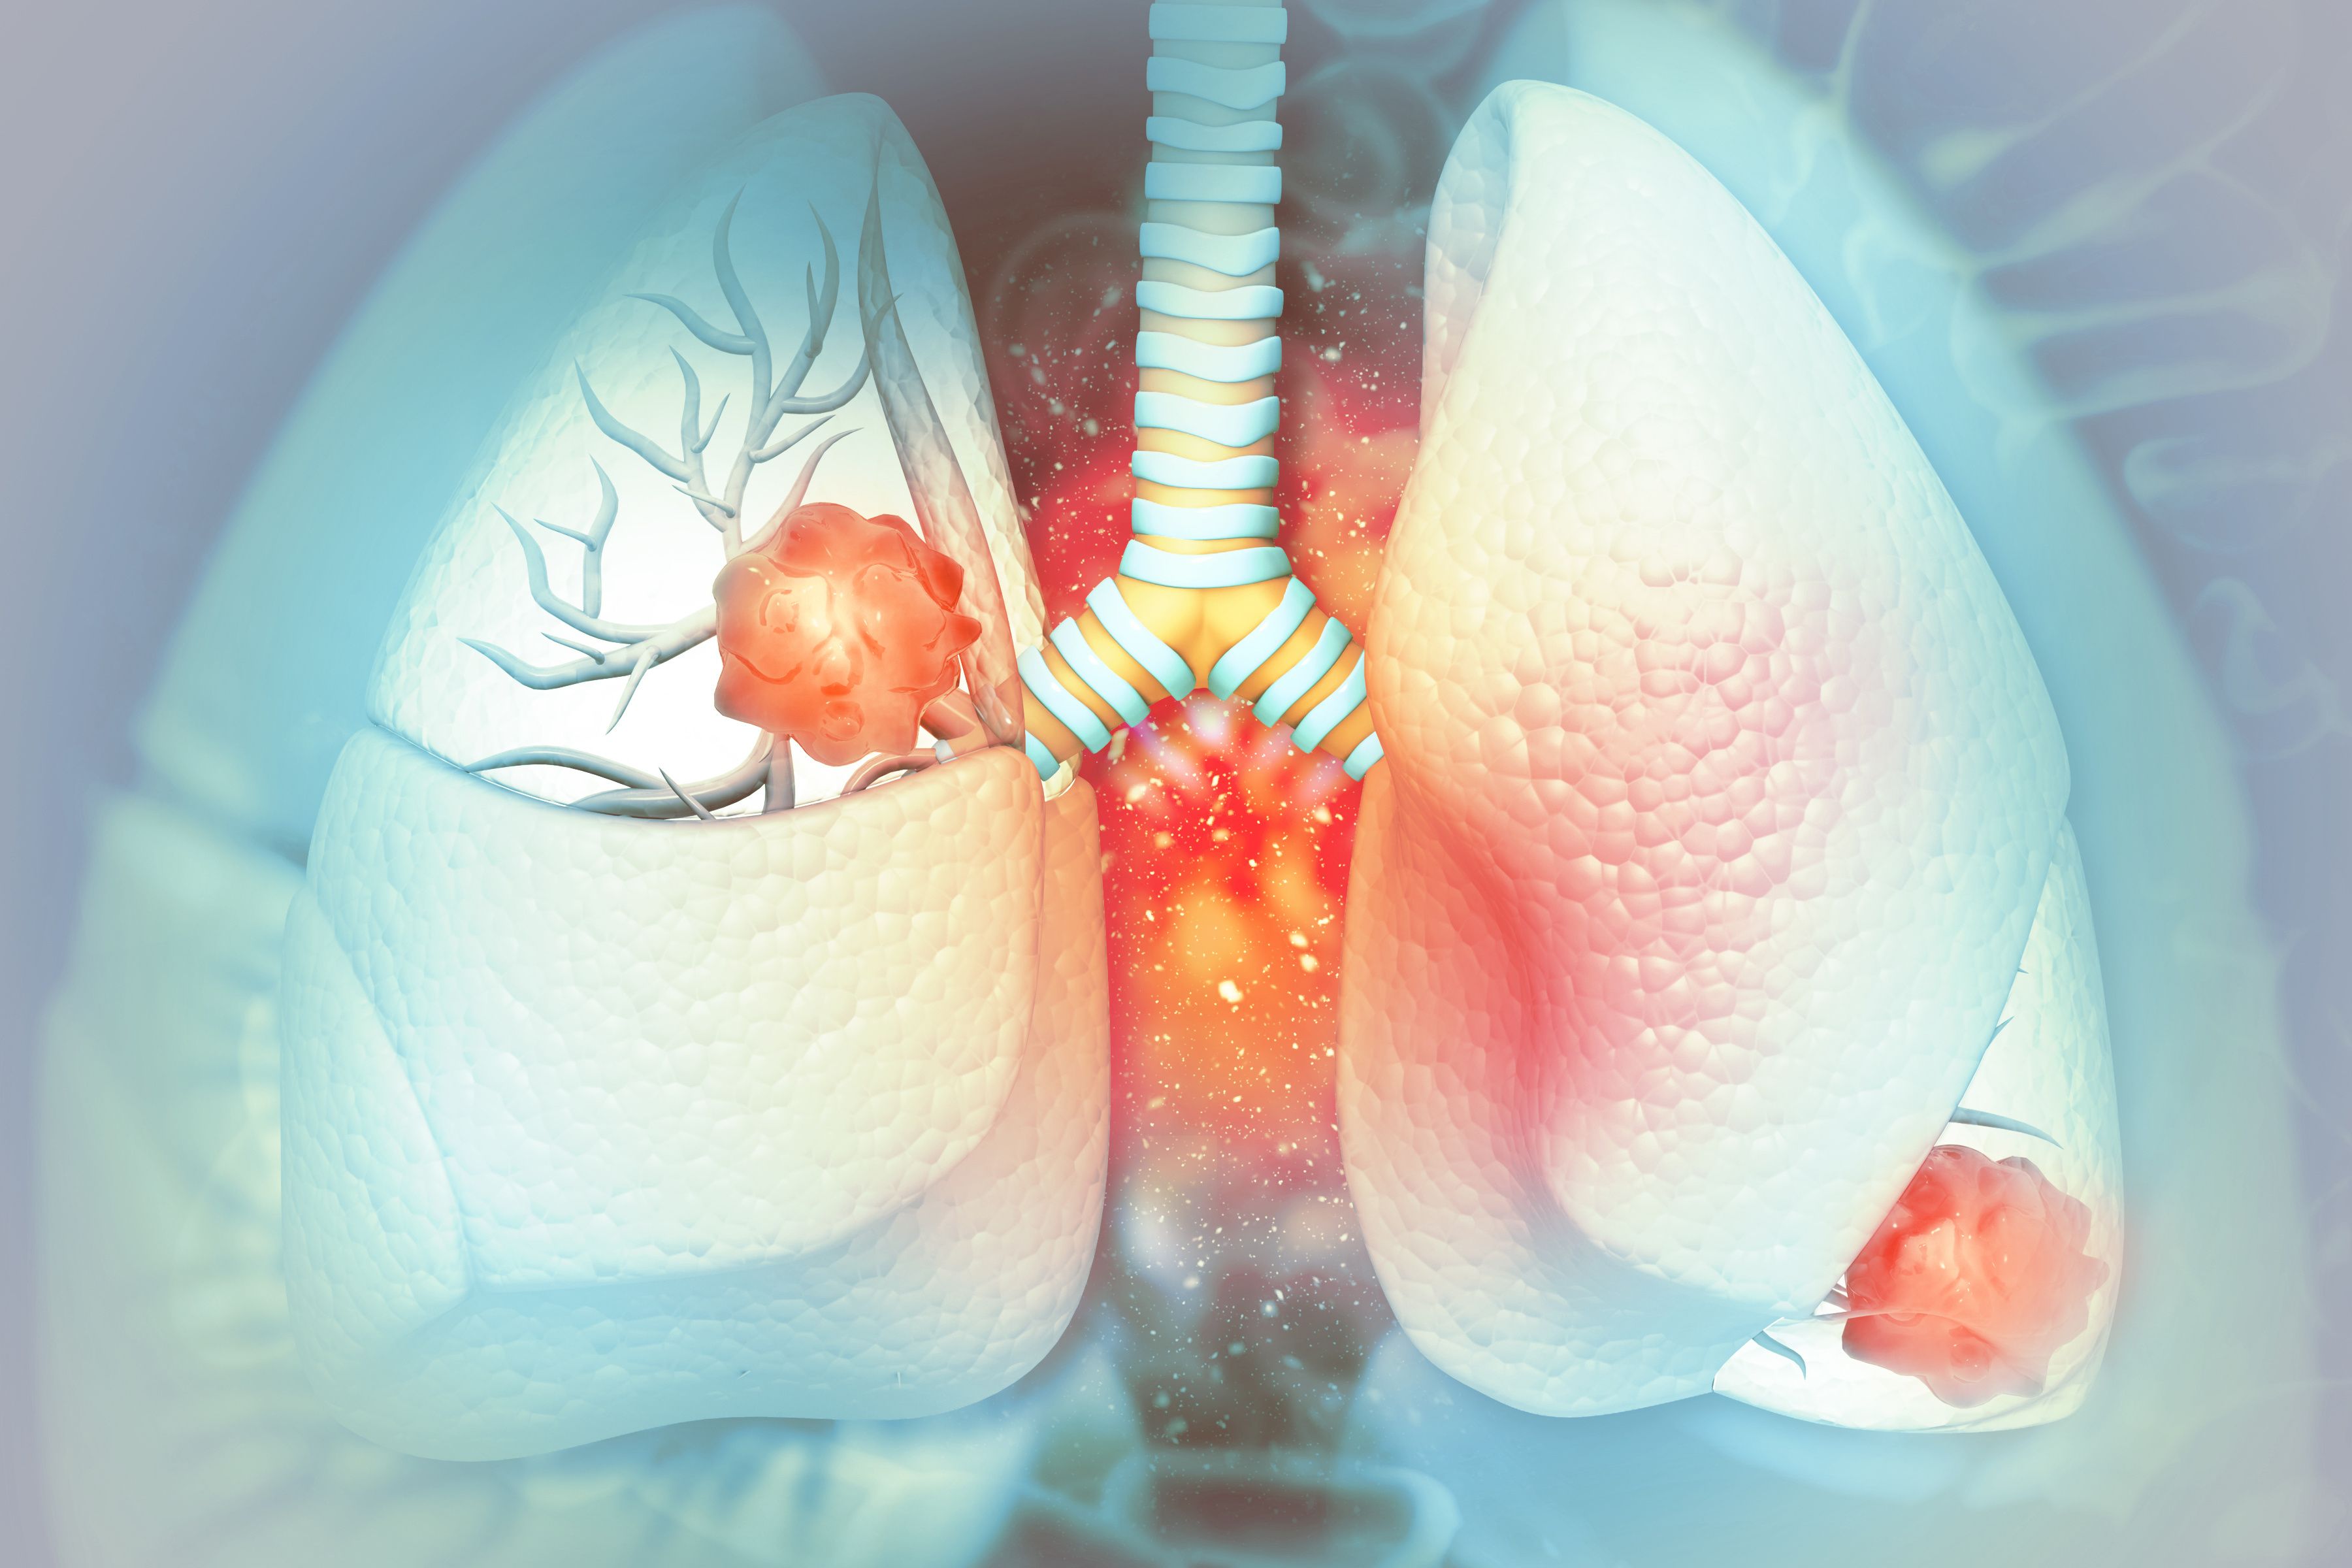

MAIA Biotechnology enrolls first patient in expansion of phase 2 clinical trial for ateganosine in advanced non─small ...

MAIA Biotechnology, Inc, a targeted therapy and immuno-oncology company focused on the development and commercialization of potential first-in-class drugs with novel mechanisms of action that are intended to meaningfully improve and extend the lives of …